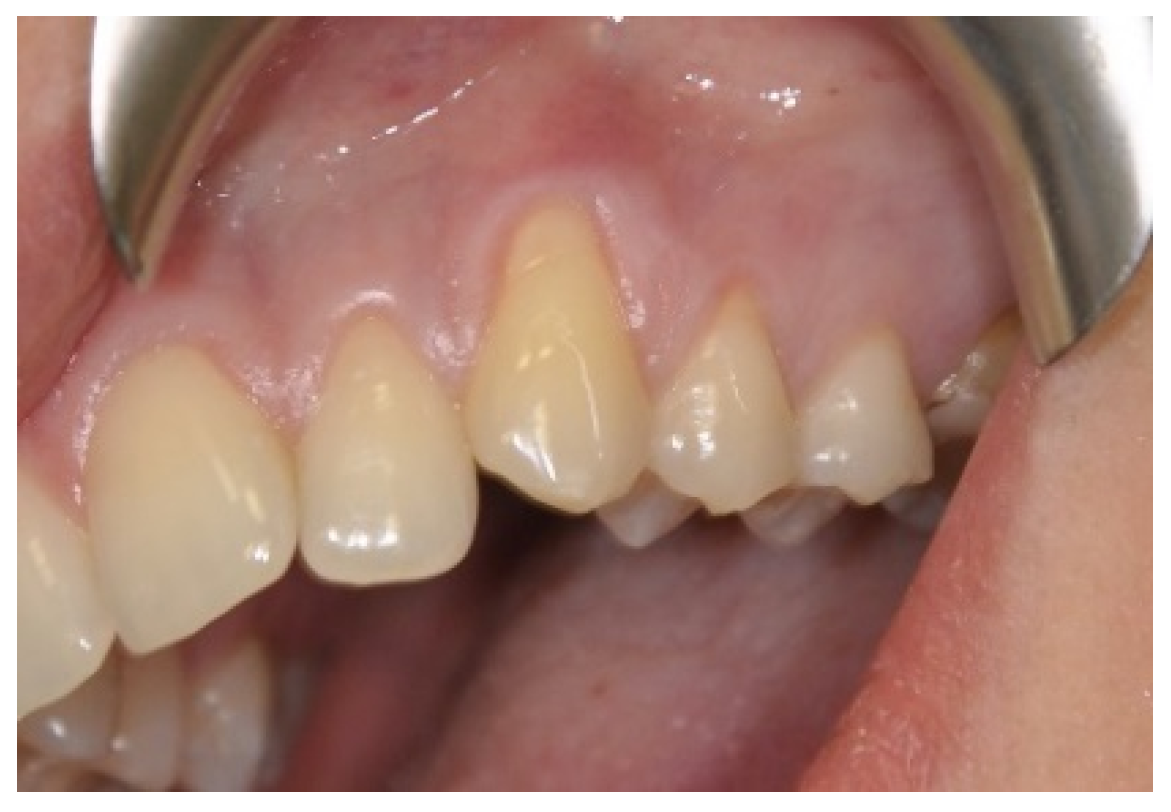

2.3. Surgical Procedures

3.1. Clinical Measurements for CAL and GRD

3.2. Clinical Measurements for GRW, PD and AG